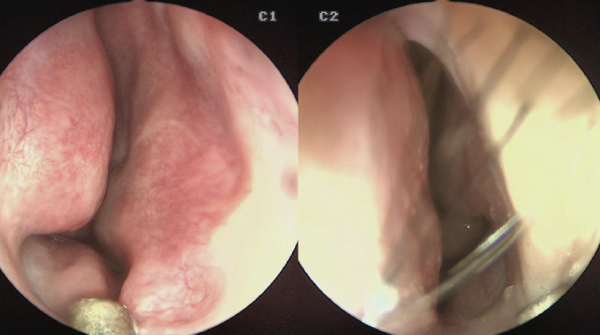

![]()

좌측에서 미단부 변형으로 인한 비밸브 협착이 관찰되었다. CT보다 내시경

검사에서 더 현저하게 나타났다

내시경 검사에서는 비중격 골부에서 연골부 상단에 걸 친 좌측으로의 만곡 그리고 비중격 미단부에서 좌측 만곡으로 인한 비밸브 협착도 관찰되어, 비중격 및 비밸브 교정술,

하비갑개점막절제술을 계획하였다.